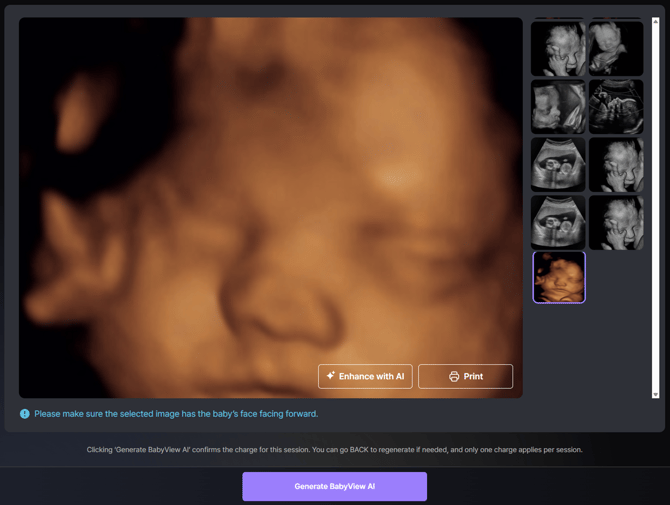

[Step 3] Choose the Image

- Select the ultrasound image you’d like to use.

- Optional: Click Enhance only if the image is extremely blurry or dark.

(This pre-enhances the input image before AI generation.)

Note: For best results, use a front-facing image of the baby’s face.

- Once ready, click “Generate BabyView AI” below.

- Processing Time: Image generation typically takes 1 to 3 minutes, depending on network speed and server load. You can stay on the page during processing — the final result will appear automatically once complete.

IMPORTANT - MUST READ: Charging Policy

Clicking “Generate BabyView AI” confirms the charge for this session.